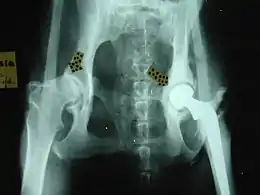

Common orthopedic surgeries in animals include:

- For hip dysplasia:

- Femoral head osteotomy

- Triple pelvic osteotomy

- Hip replacement